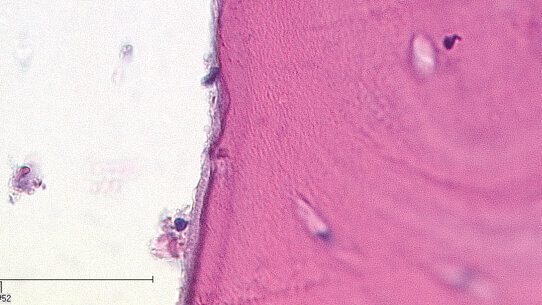

Infine, è degno di nota lo studio di Seoane et al.9, in cui il danno termale e i tipi istologici risultanti dall’uso del laser sono rilevanti per il processo di decisione sulle biopsie. Questo studio ha esaminato le ferite causate dal laser CO2 in 25 ratti Sprague, assegnati in modo random a cinque gruppi in cui le glossectomie sono state eseguite con un laser CO2 (3, 6, 9 e 12 W); e un gruppo controllo trattato con un bisturi. I campioni sono stati preparati, quindi colorati e sottoposti a uno studio a doppio cieco a cura di due patologi. Sono stati identificati il polimorfismo cellulare e nucleare, l’aberrazione nucleare e la perdita di adesione intercellulare, soprattutto negli strati basale e soprabasale dell’epitelio orale, ma non sono state osservate differenze tra i gruppi sperimentali. Nel gruppo controllo non sono state osservate modifiche istologiche o strutturali. Per tutte queste ragioni, il laser CO2 (3-12 W) dovrebbe essere considerato in grado di generare un danno epiteliale che può simulare la displasia. Questo può a sua volta portare all’insuccesso della terapia.

Non vi sono studi più ampi che forniscano evidenza dei risultati già menzionati nella sezione precedente. Pourzarandian et al.10 hanno confermato che le osteotomie eseguite con laser Er:YAG, laser CO2 o fresa chirurgica hanno dato come risultato a una maggior rivitalizzazione di osteoblasti e fibroblasti e una rivascolarizzazione più pronunciata nel tessuto trattato con laser Er:YAG. Lo studio di Martins et al.11 ha trovato che la guarigione di un’ostectomia nella mascella risulta migliorata dopo il trattamento con laser Er:YAG rispetto a ferite inflitte da una fresa chirurgica o laser CO2. Per questo motivo, sono necessari studi a lungo termine a 60 a 90 giorni al fine di fornire una maggior evidenza a supporto di questi risultati. Di conseguenza, negli ultimi anni sono stati pubblicati molti studi su questi temi. Altri studi, come quello di Rochkind et al.12 hanno confermato l’effetto positivo della LLLT sulla guarigione del tessuto osseo (vedere sezioni istologiche, Figg. 1-3).